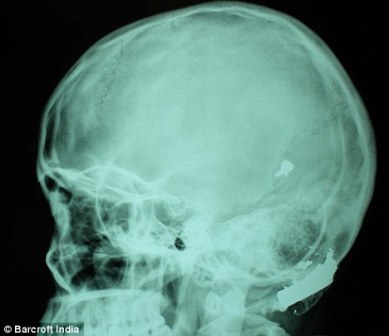

其中一顆子彈擊中她的左中耳,穿透了她的耳骨,然后擊中頭骨,嵌在了腦子里。另外兩顆子彈分別擊中她的右臂和心臟。印度Lok Nayak醫(yī)院的醫(yī)生稱,赫娜能夠康復(fù)完全是奇跡,她也足夠幸運(yùn)。她的主治醫(yī)生稱:“當(dāng)我們看到她的情況時(shí),被嚇了一跳,幸運(yùn)的是她活了下來!

這顆子彈沒有損壞大腦中控制身體機(jī)能的部分。盡管赫娜的手術(shù)很成功,但醫(yī)生表示,她還有出現(xiàn)感染和并發(fā)癥的可能。子彈毀掉了她的中耳,可能導(dǎo)致她耳聾。(楊柳)